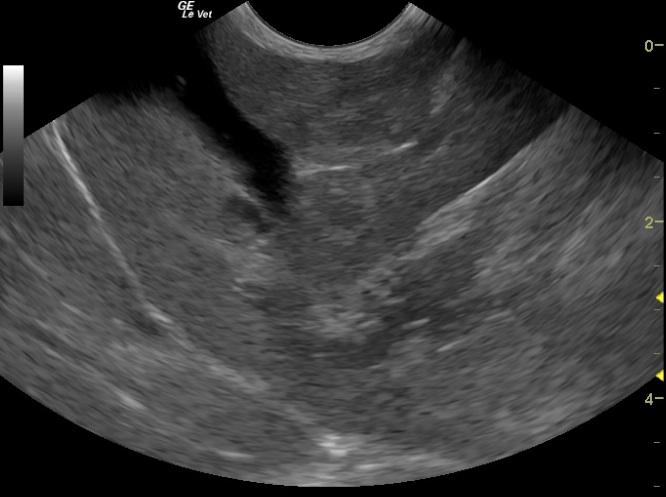

A 16-year-old Abyssinian was presented for PU/PD and anorexia. On physical examination weight loss was present. The only abnormalities on urinalysis and blood chemistry were isosthenuria and azotemia, respectively. The patient was treated with I.V. fluids, which resulted in an improvement in the azotemia after three days.